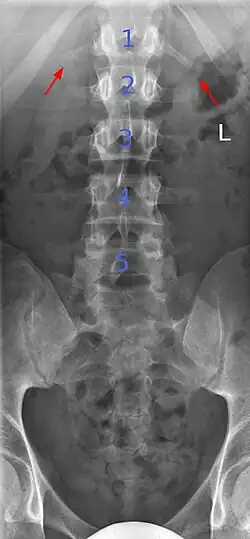

Ein Übergangswirbel (Syn.: Assimilationswirbel, Schaltwirbel[1]; engl. transitional vertebra, assimilated vertebra) ist eine angeborene Variation an den Grenzen der Wirbelsäulenabschnitte, die sich bei bis zu 35 % der Bevölkerung findet.[2] Übergangswirbel haben die Formen und Eigenschaften der angrenzenden Wirbelregionen ganz oder teilweise angenommen.

Typische Beispiele sind die Sakralisation des 5. Lendenwirbels (Lumbalwirbels) – in diesem Fall ist der 5. Lendenwirbelkörper mit dem ersten Kreuzbeinwirbelkörper ohne funktionelle Bandscheibe knöchern verwachsen – oder die Lumbalisation des 1. Kreuzwirbels, hier gibt es eine Bandscheibe zwischen dem ersten und zweiten Kreuzwirbel, so dass der erste Kreuzwirbel funktionell als zusätzlicher (sechster) Lendenwirbel anzusehen ist.

Unterschieden werden vollständige und partielle (teilweise) Übergangswirbel, je nach Stärke der Assimilation. Bei den partiellen Übergangswirbeln kommen auch Formen vor, bei denen eine Seite assimiliert ist, während die andere Seite unverändert ist, was dann zu asymmetrischen Bewegungsmustern dieses Wirbelsäulenabschnitts führen kann.